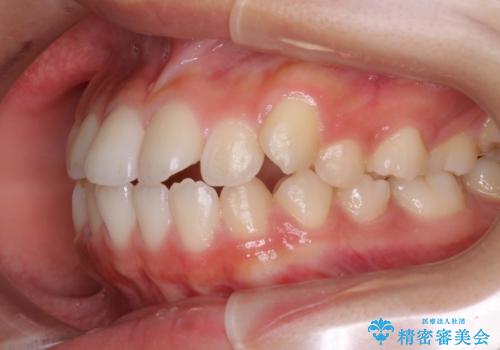

ハーフリンガル 半分裏側矯正による上下前突の抜歯矯正治療

- 20代女性

- 矯正装置

- ハーフリンガル

- 上下左右4本の第1小臼歯を抜歯する、抜歯矯正を計画した。

抜歯矯正により前歯の位置が後ろに下がり、わずかではありますが、口元に改善がみられ、歯並びもきれいに整いました。